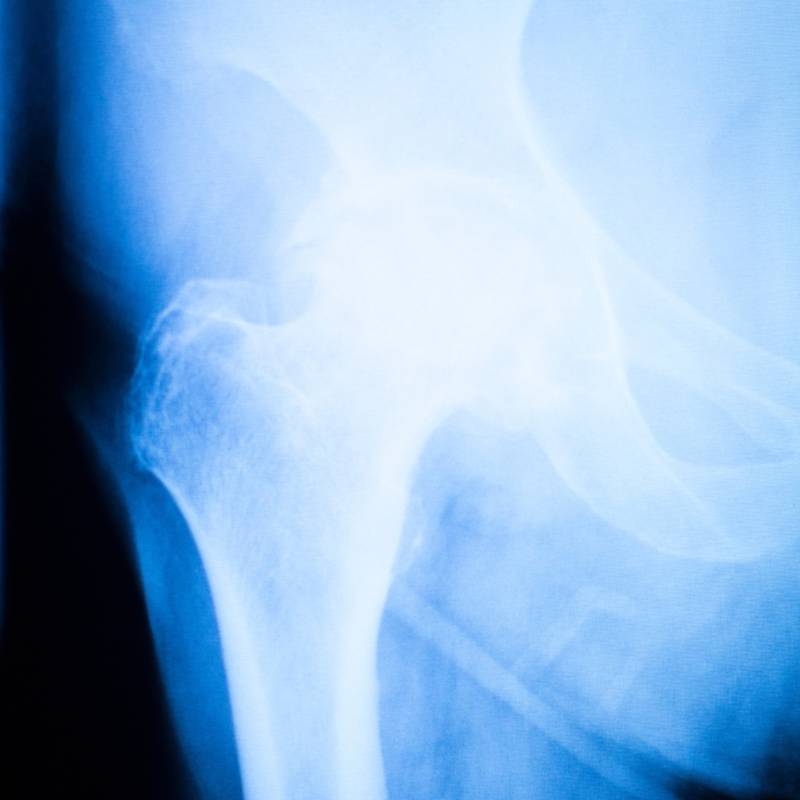

Sinar-X untuk memeriksa keadaan sendi pinggul.

Pemeriksaan sinar-X untuk menilai tulang paha.